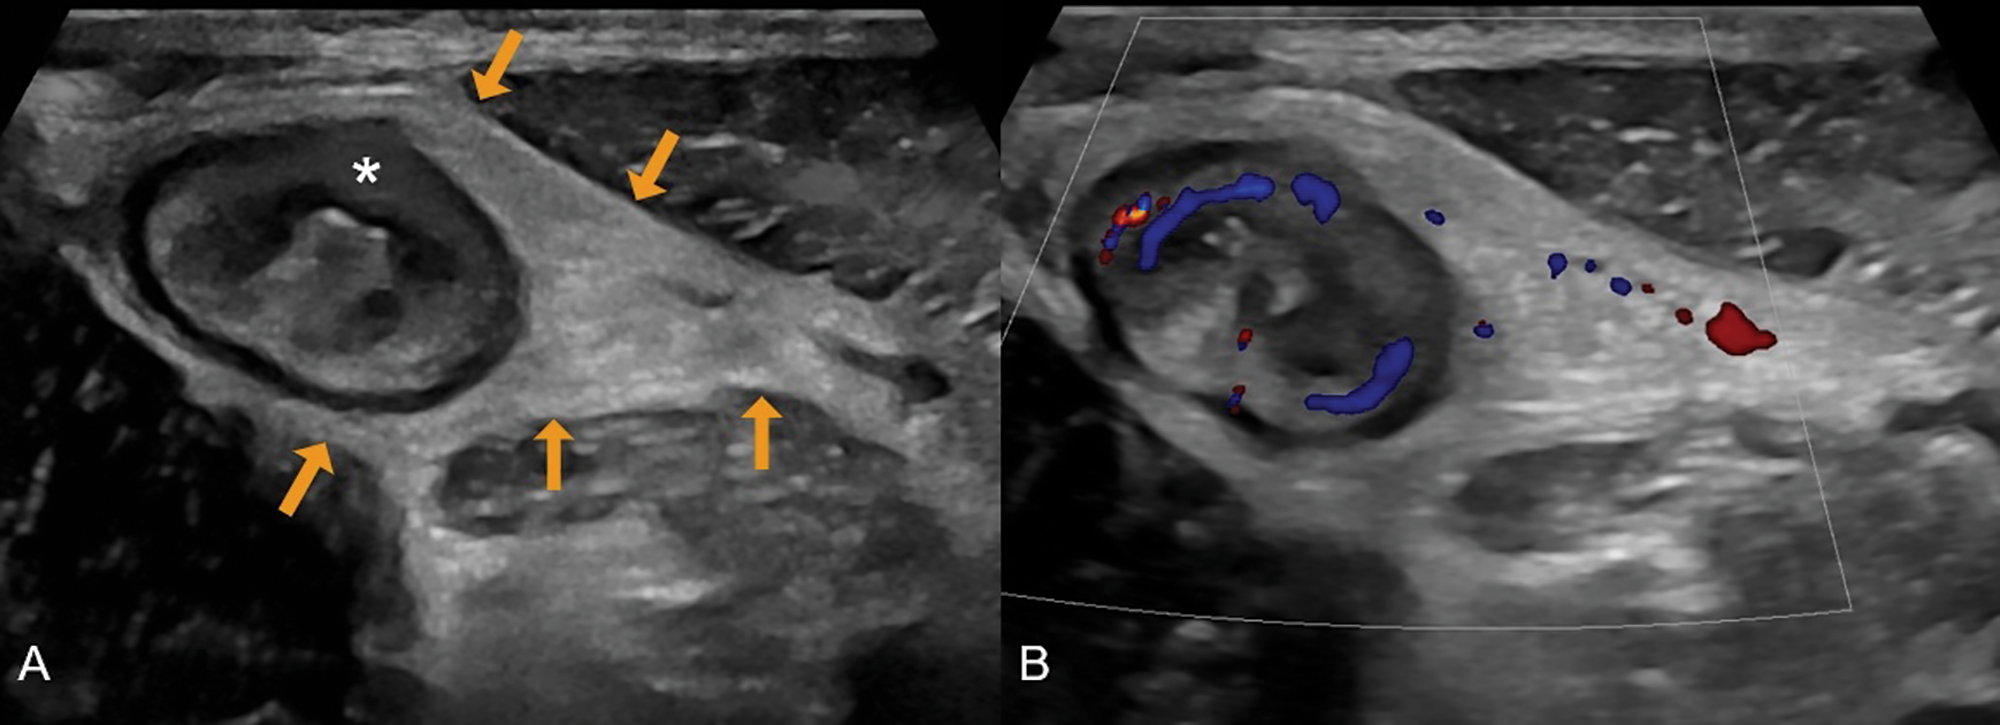

Figure 2

A 31‑year‑old male with newly diagnosed Crohn’s disease. (A) Greyscale ultrasound shows a thickened terminal ileum with extensive loss of mural stratification (asterisk) and hyperechoic fat wrapping (arrows). (B) Colour Doppler demonstrates increased vascularity in the ileal wall and adjacent inflamed fat.